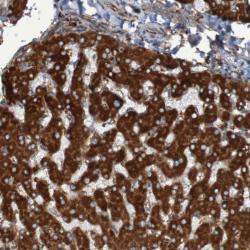

Supportive validation

- Experimental details

- Immunohistochemical staining of human liver shows strong cytoplasmic positivity in hepatocytes.

- Validation comment

- Staining pattern partly consistent with experimental and/or bioinformatic data.